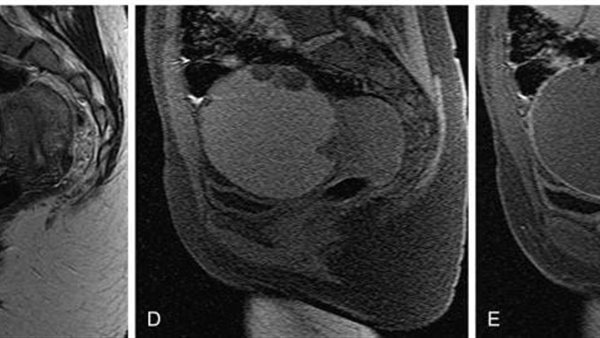

وقال الدكتور تامر مدكور، وكيل وزارة الصحة بالدقهلية، إن المريضة حضرت إلى عيادة جراحة الأورام وهي تعاني من آلام مستمرة بمنطقة الحوض، مع وجود تاريخ مرضي تضمن استئصالًا جزئيًا للرحم، وجراحة سابقة لاستئصال كيس على المبيض. وبناءً على الفحوصات والأشعة، تبيّن وجود كيس بحجم 10 سم في منتصف الحوض.